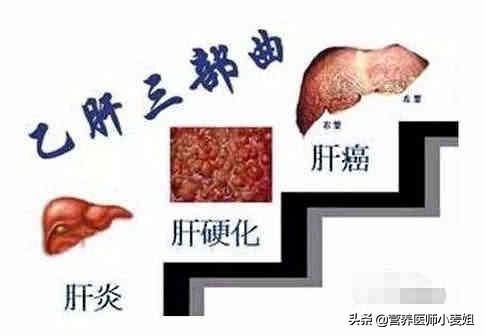

1.肝炎

B/C型肝炎、肝硬変、肝癌は、中国における肝癌発症の最も重要な3部作である。欧米先進国の肝臓がんは、アルコール性肝炎、肝硬変、肝臓がんが主な原因であり、原因は似ている。肝炎による肝細胞へのダメージがある程度蓄積されると、発がんのリスクが高くなる。

肝硬変→肝がん

中国では、肝炎→肝硬変→肝がんの3部作が存在する。海外で最も一般的なものはアルコール誘発性肝硬変。

もし肝硬変を基礎疾患とするB型肝炎の既往歴は、肝癌のハイリスク群である。画像所見で疑わしい部位やαフェトプロテインの上昇を伴う場合は、がんが存在する可能性がある。

3.B型慢性肝炎:中国ではB型肝炎ウイルスキャリアは10%に達し、肝臓がんの80%はB型慢性肝炎が原因である。肝細胞癌は慢性B型肝炎と密接な関係があり、肝炎、肝硬変、肝細胞癌は肝臓三部作と呼ばれている。B型慢性肝炎の患者さんは、定期的に肝機能とB型肝炎ウイルスDNA定量を見直し、抗ウイルス薬を内服してウイルス価を正常にする必要があります。B型慢性肝炎のハイリスク・リスク背景とハイリスク・リスク年齢段階の人々にとって、早期肝がんの定期的なスクリーニングは、傷害保険に加入し、6ヵ月ごとにチェックすることと同じである。AFP+肝臓、胆嚢、脾臓B超これにより、少なくとも80%の肝臓がんを2-125px以内に検出することができる。

- 肝硬変は肝がんの前がん病変である。わが国が世界有数の肝がん大国であるのは、B型肝炎大国であることに由来する。B型慢性肝炎は最も危険な要因です。世界では毎年約60万人が新たに肝臓がんに罹患しており、その80%が中国で発生している。B型肝炎ウイルスに感染すると慢性肝炎になり、肝硬変、そして肝臓癌へと進行する。B型肝炎は肝炎→肝硬変→肝がんの "3ステップ "で肝がんに至る。

C型肝炎も同じ経路をたどって肝臓がんに発展する。

肝がんの初期症状と慢性肝炎を区別することは難しく、慢性肝炎から肝がんへの進行を防ぐには、慢性肝炎の積極的な治療に加えて、以下のことが必要である。肝臓癌の早期発見は、α-フェト蛋白の定期的な血液検査と超音波検査で可能である。

まず第一に、中国は肝炎の国であり、肝炎、肝硬変、肝臓癌の三部作は憂慮すべきものではないという医学界の噂は、肝炎の臨床経験が肝臓癌患者へと発展した少数派である。『ウイルス性肝炎患者は長生きすればするほど、いずれ肝臓癌になる』というのは少し絶対的に聞こえるが、確かに肝臓癌の最も重要な原因因子の一つである。したがって、ハイリスクグループは定期的に検診を受け、早期診断・早期治療を行うことが重要である。